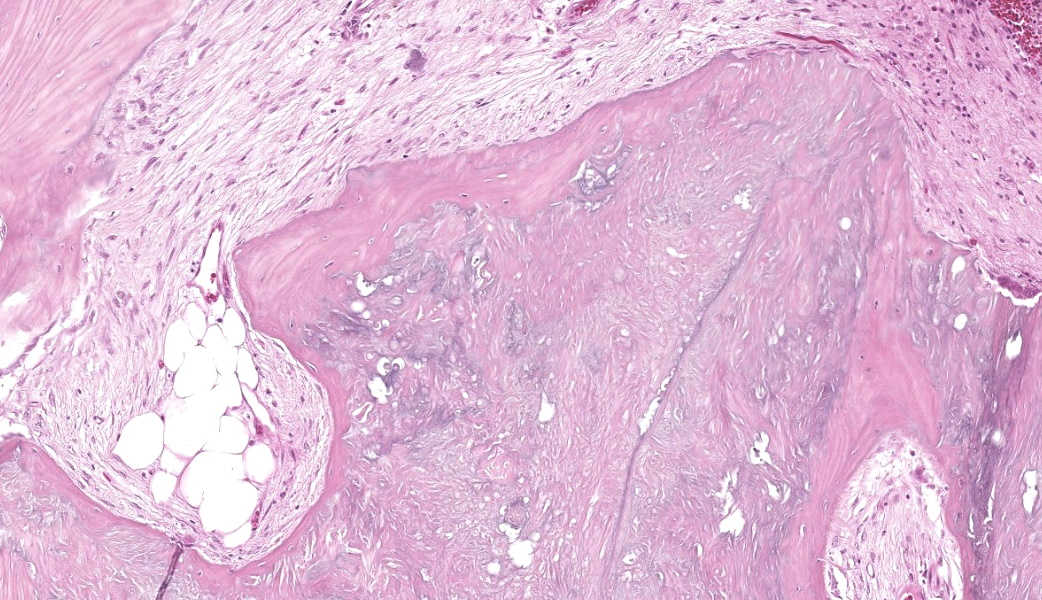

The affected skeletal muscle and subcutis were infiltrated and expanded by abundant, irregular, globoid amphophilic to basophilic material, consistent with mineralization. This mineralized material was surrounded by extensive fibrous connective tissue proliferation (fibrosis), admixed with numerous macrophages, lymphocytes, and fewer multinucleated giant cells containing phagocytosed mineral material. Scattered throughout the mass, rare foci of osteoid formation were observed, characterized by a low number of empty lacunae and necrotic osteoids undergoing remodeling. Multifocally within the mineralized soft tissue lesions, multiple tortuous blood vessels with thickened tunica media were observed. Additionally, there were areas of extensive hemorrhage, neovascularization, and granulation tissue formation infiltrating and replacing the surrounding adipose tissue.

Histologically, calcinosis circumscripta is characterized by aggregates of amorphous to granular, lightly to deeply basophilic mineralized material. These deposits are typically surrounded by macrophages, multinucleated giant cells, and occasional lymphocytes, and are delineated by fibrous connective tissue bands. As the lesion progresses, mineralization becomes more extensive and is accompanied by pronounced fibrosis. The associated inflammatory response may diminish over time, and areas of osseous or cartilaginous metaplasia may develop. In certain cases, epidermal sequestration or transepidermal elimination of mineralized material may lead to ulceration.2,3,4

In this case, the lesions were confined to the right pelvic limb, with no evidence of involvement of other organ systems. A diagnosis of calcinosis circumscripta (tumoral calcinosis) was established based on the morphological, histopathological and immunohistochemical characteristics of the lesion. Mason trichrome, Von Kossa and Perl's Prussian blue stains were performed and were positive for the fibrous connective tissue (the first one) and the globular amorphous mineral (the last two). The presence of iron within the mineralized material is intriguing. Anecdotally, the African Green Monkeys on this facility tend to present hepatic iron overload and multifocal organ hemosiderosis. Extraskeletal osteosarcoma was considered as a potential differential. However, the cellular infiltrate was immunopositive for IBA-1 (histiocytes/macrophages) and immunonegative for SATB2 (osteoblastic origin, osteosarcoma), alpha-SMA38 (mature myofibroblast, smooth muscle tumor), SOX10 (neural crest origin, melanoma and certain soft tissue neoplasms), and S100 (amelanotic melanoma and certain soft tissue neoplasms). Based on clinical history of this animal, the lesion in this case most likely represents dystrophic calcification secondary to prior traumatic injury, as has been described in other nonhuman primates. To date, neither metastatic nor idiopathic calcification has been reported in this species.

Subcutaneous fat and skeletal muscle: Mineralization, chronic, focally extensive, severe, with granulomatous inflammation and osseous metaplasia.